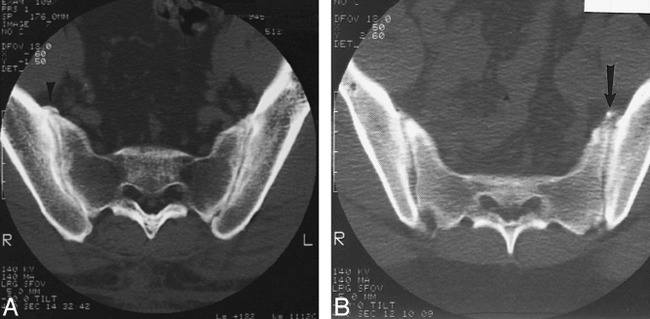

There was complete agreement between both reviewers regarding all but one case in which extension of contrast medium from the superior aspect of the joint had occurred. Both reviewers observed the leakage of contrast medium, yet one failed to document the extension of contrast medium into the adjacent L5 root canal, which was undoubtedly present on postarthrography CT scans (Fig 5). Complete concordance of findings between plain films and postarthrography CT was achieved in terms of the region of extravasation. CT was necessary to visualize the neural elements and to determine whether contrast medium contacted them.

Another pathway between the SIJ and neural structures was found in this 33-year-old patient with lower back pain and left lower extremity paresthesias.

A, Arthrogram of the anteroposterior view allowed visualization of contrast medium extravasating from the superior recess (wavy line) of the SIJ toward the L5 root canal. Symbols: 5, L5 vertebral body; S, sacral ala; IL, ilium.

B, Postarthrography axial CT scan obtained at the L5−S1 level reveals contrast medium extending to the L5 epiradicular sheath (arrows). The arrowhead points to the contralateral L5 anterior ramus. Symbols: S, sacral ala; IL, ilium. Refer to figure 4E for a comparative line drawing.